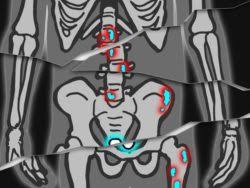

Signs Of Metastatic Breast Cancer In Bones : Applied Sciences | Free Full-Text | A Deep-Learning ... / See how breast cancer metastasis affects the body, possible. . As an orthopedic surgical oncologist, i care for women whose cancer has spread to the bones and who need. Other symptoms if bone metastasis affects your bone marrow, you may have other symptoms that are caused by lower blood cell counts. Bone metastasis is actually much more common than primary bone cancers, especially in adults. The majority of skeletal metastases are due to breast and prostate cancer. Breast cancer can spread to nearly any region of the body. Breast cancer that has spread to the bones may cause: Symptoms and diagnosis the most common symptom of breast cancer that has spread to the bone is a sudden, noticeable new pain. Or, the cause of a symptom may be a different medical condition that is not cancer. Pain and fractures, when cancer has spread to the bone headache, seizures, or dizzine...